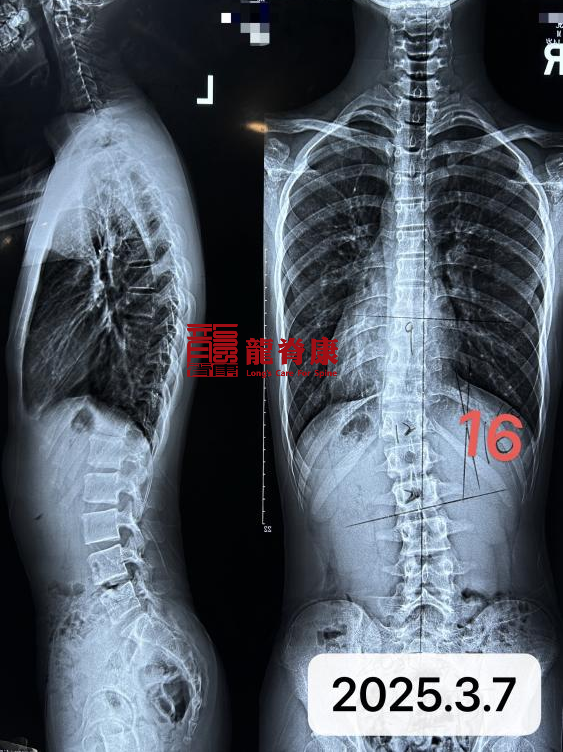

小梁同学今年14岁,在2025年3月,家长发现孩子体态异常,心急如焚立刻带着小梁前往当地医院进行检查,通过拍全脊柱X光片诊断,小梁被确诊为脊柱侧弯16°,骨龄Risser4级;外院医生建议保守治疗在家进行吊单杠,2个月后复查拍片发现侧弯度数加重,度数加重至27°。

家长和孩子也很积极配合,佩戴支具下拍片脊柱从27°推到基本变直;小孩和家长对侧弯治疗又进一步加大了信心,积极参与施罗斯训练和坚持佩戴矫形支具。